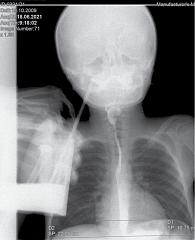

Рис. 4. Рентгенологическое исследование органов грудной клетки. Сердечно-грудной индекс – 0,48 (горизонтальный размер тени сердца – 10,75 см)

Рентген органов грудной клетки: отмечается повышенный горизонтальный размер тени сердца – 9,8 см. Сердечно-грудной индекс – 0,50 (рис. 6).